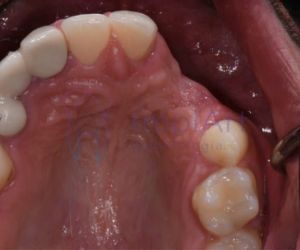

Segundo o Dr Roberto Markarian, implantodontista, s grânulos de Fordyce são pequenas glândulas sebáceas que podem aparecer na superfície da pele, especialmente nos lábios e na mucosa bucal. Eles são frequentemente confundidos com outros…